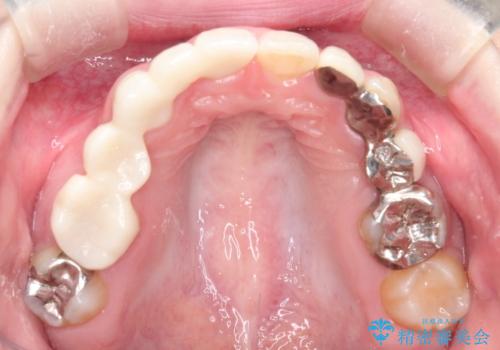

- 昔装着したかぶせ物が、不自然なのでやりかえたいとのことで来院されました。

前歯にレジン前装冠(保険内)が装着されており、自然な透明感がありません。

また奥歯にまたがるブリッジも金属のもので、適合もよくありませんでした。

オールセラミックによるやりかえを行いました。

色調もまわりの歯に合わせて、形態も患者様のご希望に沿うように製作させていただきました。